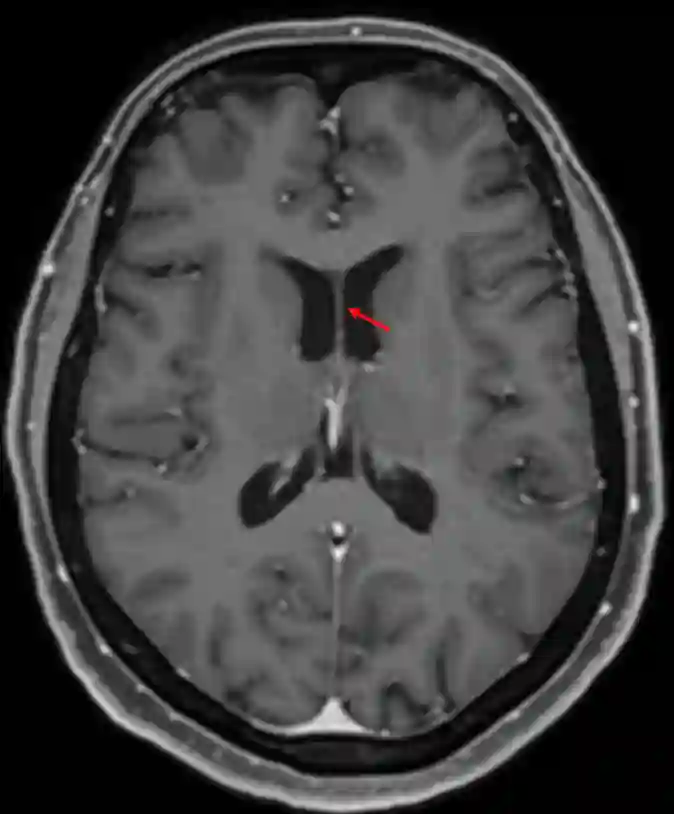

Septum pellucidum im axialen MRI (T1 Sequenz mit Kontrastmittel).Das Septum pellucidum im coronarem MRI Schnitt (T1 Sequenz mit Kontrastmittel).

Septum pellucidum im axialen MRI (T1 Sequenz mit Kontrastmittel).